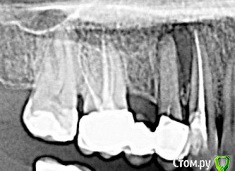

полосатая Опубликовано 3 августа, 2016 Поделиться Опубликовано 3 августа, 2016 (изменено) Здравствуйте.Обратилась к стоматологу по поводу свища- гранулемы между 3-м и 4-м зубами справа на верхней челюсти.Примерно 3 месяца ходила на лечение,закладывали кальций+йод.Сейчас зубы подготовлены под протезирование(пока временное ) с пластмассовым мостом.Каналы заполнены гуттаперчей,зафиксированы вкладки.Есть сомнения по поводу качества пломбирования каналов и фиксации вкладок: Прошу оценить качество работы. Может, пока на поздно нужно переделать?Зубы очень хочется сохранить.Фрагмент панорамного снимка: Изменено 3 августа, 2016 пользователем полосатая Ссылка на комментарий

anvladd Опубликовано 3 августа, 2016 Поделиться Опубликовано 3 августа, 2016 (изменено) По поводу 6- вкладка в небном корне, пустота в 4 это нормально.Свищ есть? Что то беспокоит? Изменено 3 августа, 2016 пользователем anvladd Ссылка на комментарий